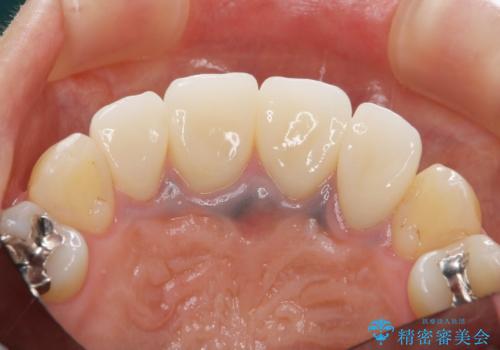

金属のフレームを用いるクラウンは色調が暗くなる傾向にありますが、セラミッククラウンに置き換えたことで自然な明るさ、審美性を取り戻すことができました。